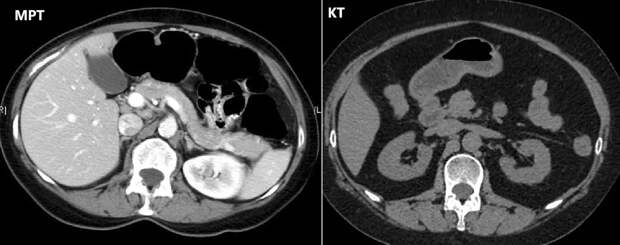

МРТ или КТ брюшной полости?

Давайте сравним методики, чтобы понять, какая из них вам требуется.

Это два мощных метода, которые имеют свои особенности, преимущества в зависимости от клинической ситуации.

МРТ подходит для оценки мягких тканей печени, поджелудочной железы, кишечника, других органов. Она не использует ионизирующее излучение, что делает его безопасным у людей с повышенной чувствительностью к радиации. Применяется для выявления опухолевых процессов, воспалений, изменений в мягкотканных структурах, для наблюдения за состоянием после операций. Процедура занимает много времени. На всем ее протяжении требуется неподвижность пациента, что затруднительно при клаустрофобии или детям.

С помощью КТ брюшной полости врачи получают результаты быстро. Ее используют для оценки костных структур, кровоизлияний, травм, заболеваний, связанных с плотными тканями (кишечник, крупные сосуды). Технология показана в экстренных ситуациях, когда нужно быстро получить изображение для принятия решения о лечении при травмах, острых заболеваниях. Компьютерная томография использует рентген, что ограничивает его использование для больных, требующих многократных обследований, несовершеннолетних. Оно менее информативно для диагностики патологий мягких тканей.

Выбор между методиками зависит от клинической ситуации, целей исследования, особенностей обследуемого. Иногда, чтобы получить полную картину, назначают оба способа.